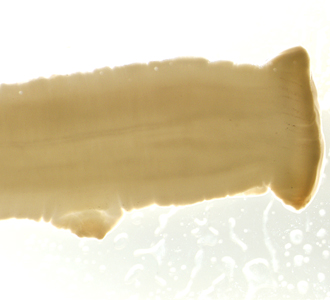

The DPDx Team received a pair of proglottids from a state health lab for cestode confirmation and identification. The specimens were submitted in 70% ethanol and measured on average 12.0 mm long by 3.0 mm wide. The proglottids were reportedly found in the feces of a 43-year-old woman with no documented international travel. Figures A and B show one of the proglottids. Figures C and D show the same proglottid after soaking in lactophenol for several hours. What is your diagnosis? Based on what criteria?

Figure B